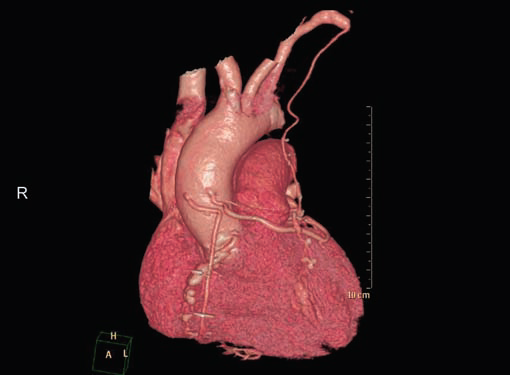

CT is the preferred tool of investigation of coronary bypass grafts (Fig. 9). Reversed saphenous vein grafts (SVGs) are optimally studied consistently. Anastomotic sites are studied effectively. However, distal anastomosis of venous graft to obtuse marginal branch (OM) is relatively difficult to evaluate because of diminishing caliber of native vessel. Arterial grafts pose a small challenge due to artifacts of associated surgical clips (Figs 10A and B). Ostium and proximal part of graft are assessed well. However, distal anastomotic site may be difficult to assess on occasions. RIMA graft, posterior descending artery (PDA) graft, gastroepiploic artery graft can also be studied. Stenosed venous grafts